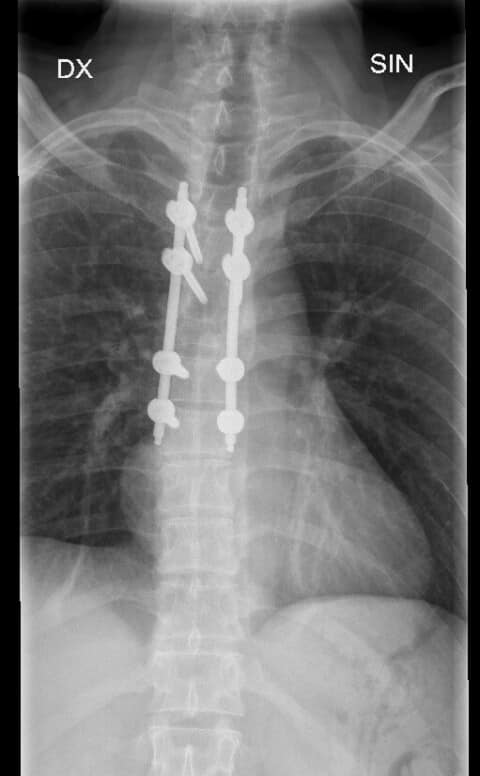

Pacientam tika veiktas mazinvazīvas mugurkaula operācijas:

1. Mugurkaula krūšu daļas lūzuma stabilizācija perkutāni mazinvazīvi t.i. stabilizējošās skrūves un stieņi tika implantēti caur atsevišķiem maziem griezieniem, nevis plaši atverot brūci. 2. Mugurkaula otrā kakla skriemeļa stabilizācija ar speciālu pielāgotu kompresijas skrūvi.

Mazinvazīvā metode, kad operācija pacientam tiek veikta caur vairākiem nelieliem griezieniem, TOS tiek praktizēta jau daudzus gadus, tomēr šāda veida operācija, kad vienam pacientam tiek vienlaicīgi maztraumatiski izoperēts un nofiksēts gan mugurkaula kakla daļas skriemeļa lūzums, gan mugurkaula krūšu daļas nestabils lūzums, ir notikusi Latvijā pirmo reizi, stāsta TOS.